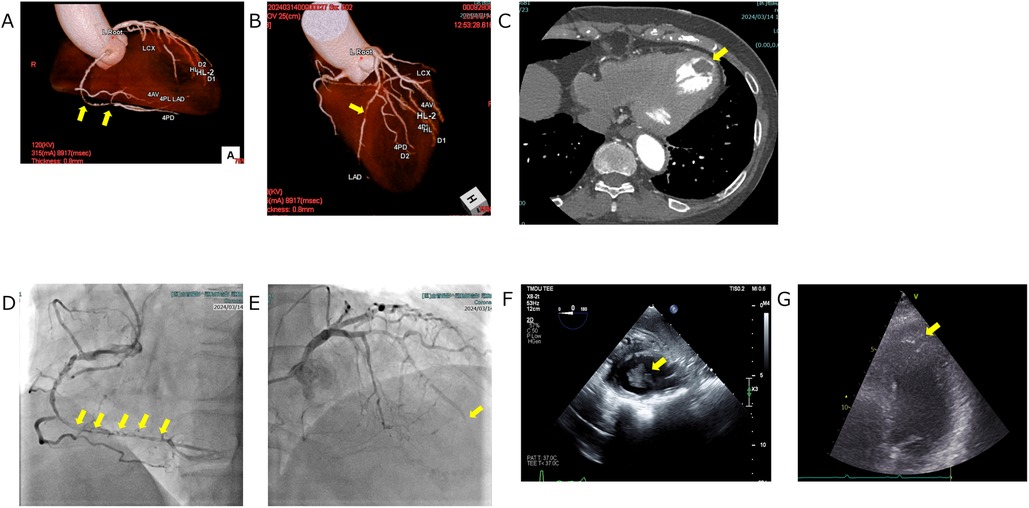

In our department, various antidepressants were prescribed according to standard protocols, but these were not sufficiently effective. In June 2023, the patient began to complain of exertional toothache and chest pain. She reported that the symptoms were consistently provoked by walking or climbing and typically subsided within 5–6 min of rest, suggesting an exertional pattern. A chest CT performed in July 2023 revealed no abnormalities. In January 2024, her exertional toothache worsened, and she reported no relief with loxoprofen. A Holter ECG was repeated at her primary care clinic in February 2024, again showing no abnormalities. However, an evaluation at a specialized cardiac imaging center revealed 90%–99% stenosis of the left anterior descending artery (LAD) and right coronary artery on coronary CT and echocardiography, as well as a thrombus in the left ventricular apex. However, evaluation at a specialized cardiac imaging center revealed occlusion of LAD #7 and 90%–99% stenosis of right coronary artery on coronary CT, and a thrombus in the left ventricular apex on echocardiography (visualized as a well-defined echogenic mass adherent to the thinned, akinetic/dyskinetic apical endocardium and distinct from the blood pool). Figures 2A–C Coronary angiography was then performed at our hospital, leading to a diagnosis of unstable angina, and she was urgently admitted to the cardiothoracic surgery ward. Subsequent coronary angiography and echocardiography performed at our hospital showed similar findings, and the diagnosis was made that emergency surgery was indicated. Figures 2D–G A Dor procedure—left ventricular reconstruction in which the infarcted, thinned, akinetic/dyskinetic aneurysmal segment is excised and the ventricular cavity is reshaped to restore more physiologic geometry and reduce stasis-related thrombus risk—was performed to remove the apical thrombus, and coronary artery bypass grafting was carried out. Specifically, a bypass from the Left Internal Thoracic Artery to LAD was created, and a bypass from the Saphenous Vein to the Posterior Descending artery was formed. Preoperative D-Dimer was 1.1 μg/ml, creatine kinase–MB (CK-MB) 2.3 ng/ml, and troponin I 17 ng/ml; postoperatively, CK-MB was 5.3 ng/ml and troponin I 2.285 ng/ml.

Figure 2. Cardiovascular imaging. (A,B) Coronary CT angiography depicting focal coronary stenoses (yellow arrows). (A) Volume-rendered view of the right coronary artery demonstrates a discrete mid-segment narrowing. (B) Three-dimensional reconstruction of the left coronary system shows a critical lesion in the proximal left anterior descending artery. (C) Axial contrast-enhanced chest CT illustrating a left-ventricular thrombus (yellow arrow). The thrombus appears as a well-defined hypodense filling defect adherent to the endocardial surface of the left ventricle. (D, E) Coronary angiography depicting critical coronary lesions (yellow arrows). (D) Right coronary artery injection demonstrates a series of tight, tandem stenoses extending from the mid- to distal vessel. (E) Left coronary angiogram shows an abrupt cut off of the left anterior descending artery arising from the left coronary artery, indicating complete occlusion at the site marked by the yellow arrow. (F,G) Echocardiographic visualization of a left ventricular thrombus: on both transesophageal (F) and transthoracic (G) views, the thrombus appears as a well-defined echogenic mass attached to the thinned, akinetic/dyskinetic endocardial surface and acoustically distinct from the blood pool (yellow arrows).